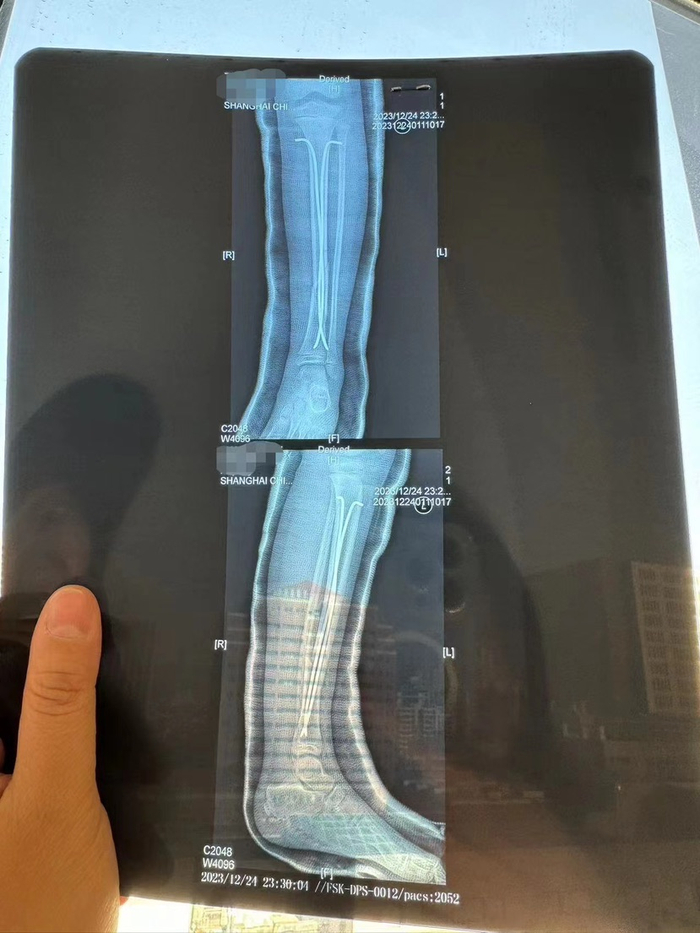

图说:乐乐左腿植入了两根髓内钉,目前只能躺在床上。 陈丽娜 摄

12月24日,这场意外刷屏了互联网,而这距离疯狂动物城正式开幕仅四天。孩子被送往医院后,左腿植入了两颗髓内钉,目前只能躺在床上。

乐乐被送到上海儿童医学中心后,门诊初步诊断为左腿胫骨骨折,并在当天做了6个小时的全麻手术,左腿里放置了两根髓内钉。

图说:事发当日乐乐做了6小时全麻手术,左腿植入了两根髓内钉。图源:受访者